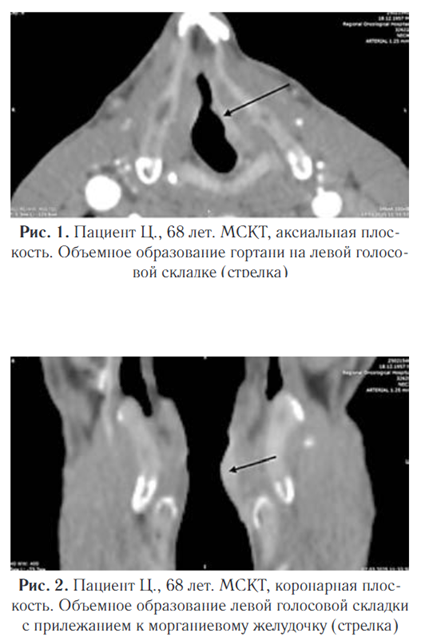

Согласно инструкции, расчет дозы в миллилитрах на килограмм массы тела не предусмотрен. Для взрослого пациента рекомендуется вводить 100–150  мл препарата. В связи с этим мы применяли Ниоскан 350 в дозировке 100 мл для данного пациента. По данным мультиспиральной компьютерной томографии шеи: на левой голосовой складке определяется объемное образование смешанного типа роста, занимающее всю длину голосовой складки, прилежит к  морганиевому желудочку (закрыт), вестибулярная складка без признаков роста (рис. 1, 2)

Плотность новообразования в  нативную фазу исследования составила 47 HU, в  артериальную фазу отмечено равномерное накопление контрастного вещества до 111 HU, в венозную фазу вымывание контрастного вещества — 102 HU. Особое внимание уделялось визуализации степени инфильтрации опухоли в  морганиев желудочек и вестибулярную складку, что позволяло объективно оценить степень вовлеченности окружающих тканей и  прогнозировать дальнейшее течение патологического процесса. Размеры образования: в аксиальной плоскости 18,5 мм (длина), 4,1 мм (ширина), в коронарной плоскости 17,8  мм (вертикаль) (рис.  3, 4).